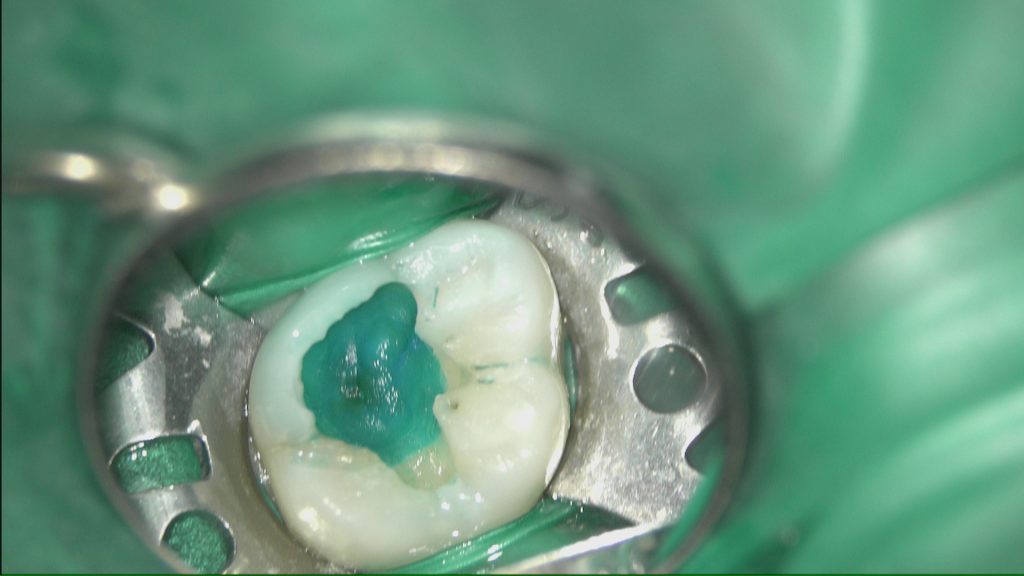

う蝕検知液を使いカリエスを慎重に除去していきます。

虫歯の取り残しは問題外です(^^;)

やはり最初の診断通り歯の神経まで到達していました。

MTAセメントを使わない場合はこの時点で抜髄(神経を取る治療)です。